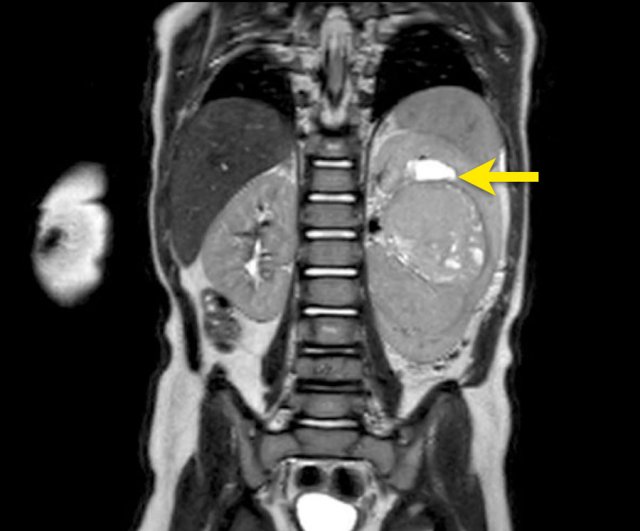

Nephroblastoma of the left kidney in a three-year-old boy. The remnant of the kidney is draped over the tumor (“claw sign” arrow). The tumor is rather homogeneous with some cystic areas.

Continue with the MRI.

Nephroblastoma of the left kidney in a three-year-old boy. A bilobar tumor is present in the interpolar region. There is a dilated calyx in the upper pole (arrow).